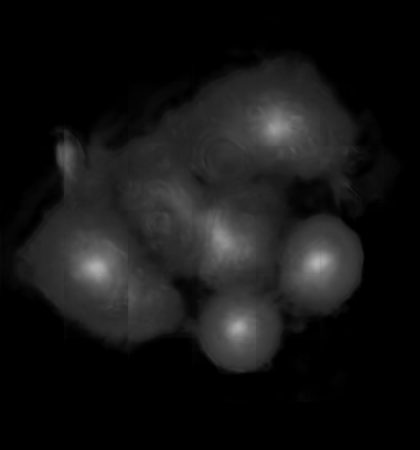

![]() |

| (a) | (b) |

| (c) | (d) |

For an example subimage given in Fig. 2a, these distance definitions are illustrated in Figs. 2b and 2c, respectively. The inner distance definition well indicates the cell centers since it uses the Euclidean distances from pixels to their closest cell centers. However, as it uses the centers as the reference point, the distance decrease from a center to its boundaries is the same for all directions and for all cells. Thus, when it is used alone, this definition imposes a circular and one-sized shape on the cells, as also seen in Fig. 2b. On the contrary, since the normalized outer distance is calculated with a reference to a cell boundary, this decrease may differ from one direction to another as well as from one cell to another, depending on the shape and size of the cell. Thus, it better preserves the morphological characteristics of cells, as seen in Fig. 2c.

The proposed DeepDistance model considers cell detection as a multi-task regression problem that estimates two distance maps from the RGB image, one for formulating the main task of cell detection and the other as an auxiliary task with the motivation of more effectively learning the main task. The FCN architecture given in the previous section is designed to learn these two regression tasks at the same time. This section discusses how this model can be extended to cover more auxiliary tasks, concurrent learning of which may further increase the performance of the main task. For this purpose, this section implements an extended version of the DeepDistance model that comprises an additional task of cell pixel classification. This additional task aims to construct a classification map (as shown in Fig. 2d) from the shared features of the encoder path111To take overlapping cells apart, and hence to obtain an improved map, cell boundaries are widen and subtracted from the classification map. This improved map is also used in the comparison methods to make fair comparisons.. Note that here, instead of defining another regression problem as the additional task, we use a classification problem in order to demonstrate that the model can easily be extended to cover the auxiliary tasks related with regression as well as classification.